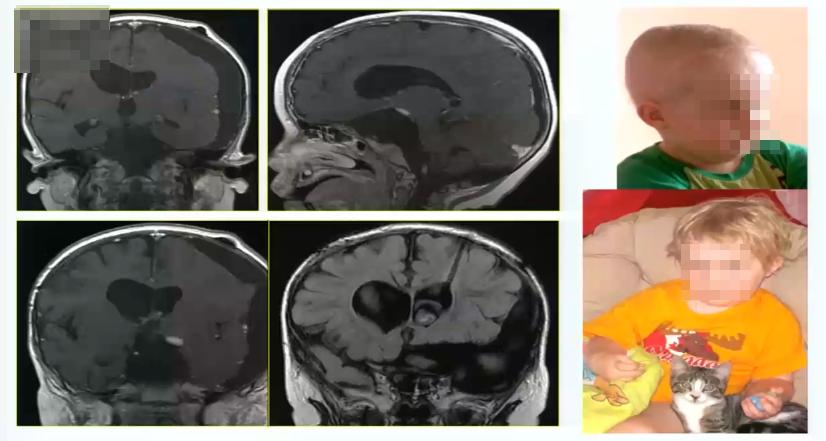

视路胶质瘤全切手术病例5:

11岁男孩,3个月大时出现首次症状(拒绝喂养),7岁时出现性早熟和过度疲劳。10岁时经翼点入路部分切除肿瘤,诊断为毛细胞性星形细胞瘤。第二次经蝶手术进行囊肿抽吸,然后用卡铂化疗,无局灶性神经损伤。肿瘤仍有残余,孩子父母便寻求巴特朗菲教授的治疗,最终巴教授和dirocco教授共同为其手术。

术中情况: 前纵裂入路全切肿瘤,下图为术中核磁检查。

术后情况: 术后出现并发症,血钠下降非常厉害,术后一周还出现癫痫大发作。通过内科治疗,逐渐恢复。因此巴特朗菲教授表示一定要注意病人术后血钠水平和激素水平的变化。